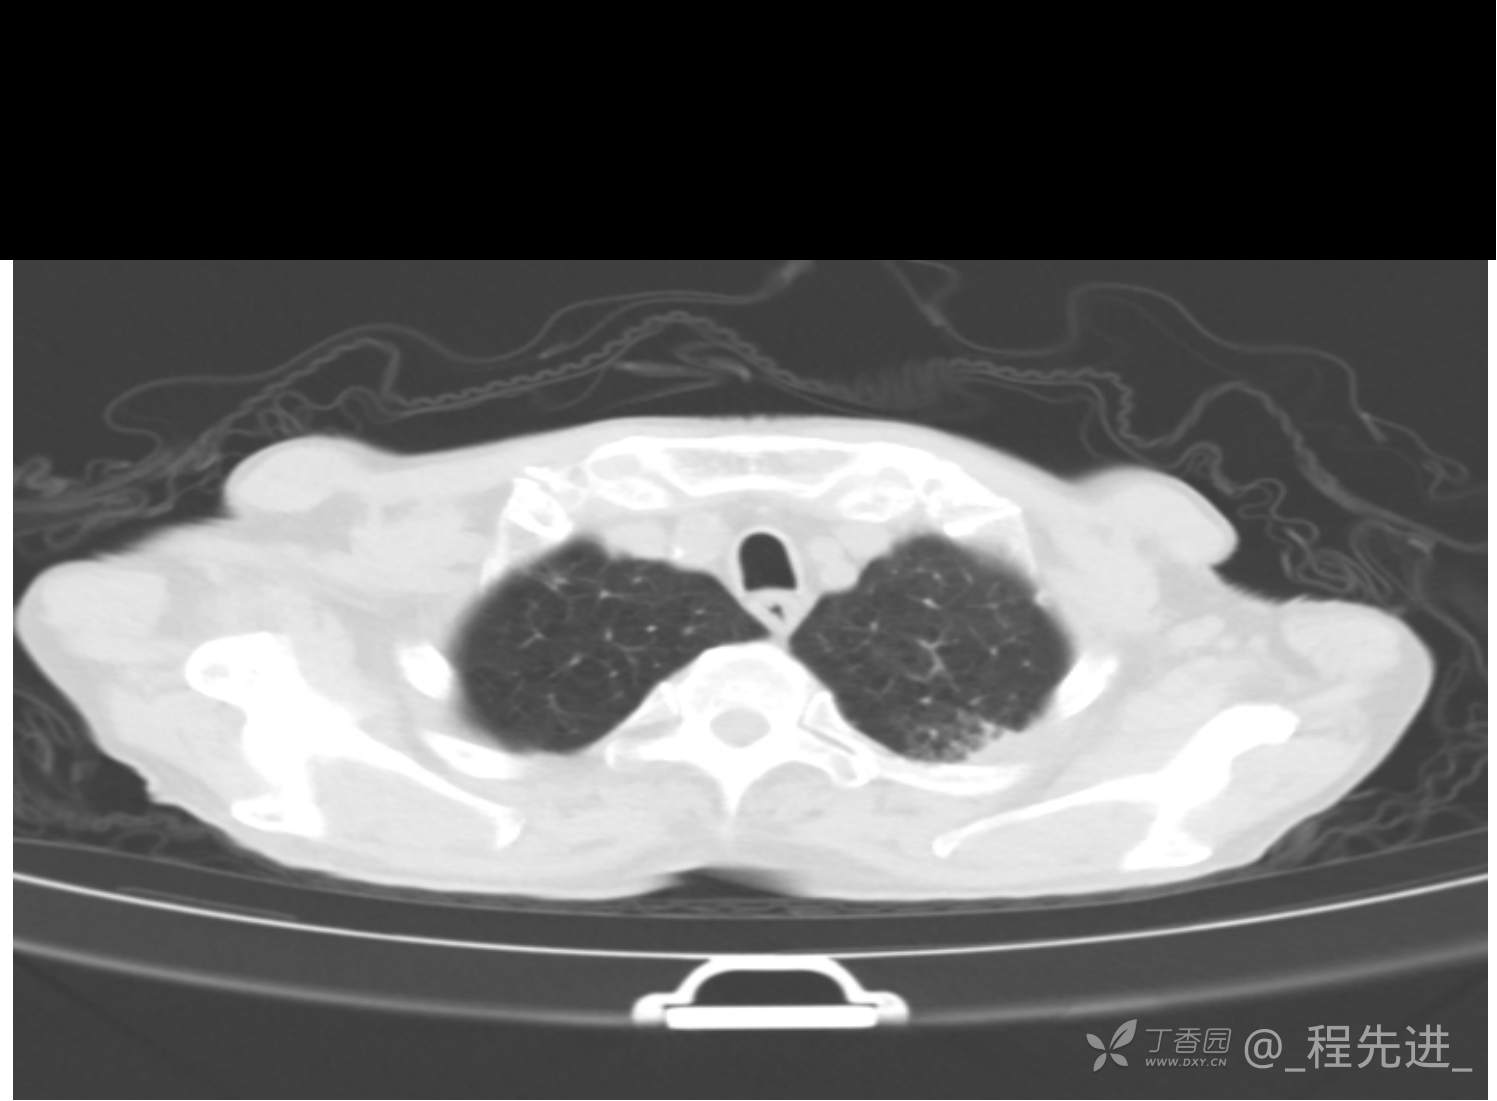

患者性别:男

患者年龄:81岁

简要病史:反复咳嗽、咳痰20余年,加重1周。两肺呼吸音低,可闻及散在干湿啰音。